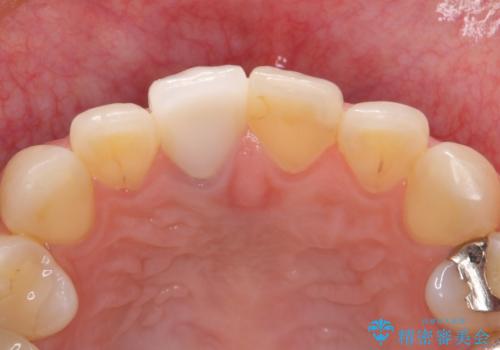

前歯のクラウンは一度修正し、患者様の理想とする色味や形態を追求しました。

天然歯と見紛うほどの自然な仕上がりに喜んで頂けました。

ジルコニアクラウンの繊細なグラデーション・透明感は熟練した技工士さんの技術の賜物です。

右上1:ジルコニアクラウン スペシャル

右上5:ジルコニアクラウン スタンダード